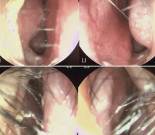

Cleft nose는 코 성형에 있어 도전적인 문제이다. \특히 비중격과 nasal spine 주변의 구조적 결함으로 인해, 비중격 교정 그리고 결손된 bone과 비익연골의 management를 동시에 시행하는 것이 key point라 하겠다.Cleft nose는 단순한 외형적 문제를 넘어, 환자의 삶의 질에 깊은 영향을 미치는 요소이다. 코의 구조적인 문 제로 인해 호흡이 불편해지고, 만성적인 코막힘과 발음 장애가 발생할 수 있다. 이러한 신체적 불편함은 일상 생활에서 지속적인 피로감과 집중력 저하로 이어질 수 있으며, 특히 성장기 어린이나 청소년에게는 학업과 사회생활에 영향을 미칠 수 있다.얼굴 중앙에 위치한 코의 비대칭은 환자의 자존감에도 큰 영향을 준다. 타인의 시선이 부담스럽거나 자신의 외모에 대한 부정적인 인식을 갖는 경우가 많으며, 이로 인해 대인관계에서 소극적인 태도를 보이기도 한다. 특히 사회적 활동이 활발해지는 청소년기에는 이러한 심리적 위축이 더욱 두드러질 수 있다따라서 cleft nose의 교정은 단순한 미용적 접근이 아니라 환자가 신체적, 심리적, 사회적으로 보다 건강한 삶을 살 수 있도록 돕는 중요한 과정이다. 기능적인 개 선과 함께 자연스러운 외형을 회복함으로써, 환자가 더 자신감 있는 모습으로 사회에 나아갈 수 있도록 지원하는 것이 수술의 궁극적인 목표라 할 수 있다 Cleft Nose와 비중격 변형 케이스수술 전 사진. 연골부에서 우측의 사비가 관찰된다. 여러 검사상 흡기 시 좌측 비익연골의 허탈과 좌측 cleft palate로 인한 cleft nose가 확인되었다.2005년생 여성 환자가 지속적인 코막힘, 특히 흡기 시 코막힘과 콧물을 주요 증상으로 내원하였다. 수술 전 이학 검사 에서 좌측에서 우측으로의 사비가 보였으며, 좌측 비주가 짧고 비주 아랫부분이 우측으로 전위된 모습을 보였다. 또 한 좌측 비공이 낮고 퍼져 있으며, 정면에서 좌측 비공저의 파임이 관찰되었다. 우측 비공은 좁고 높은 양상이었다.수술 전 CT 사진. 비중격 상단부의 좌측으로 만곡이 관찰되었다.수술 전 CT 사진. 비중격 미단부가 우측으로 전위된 모습이 관찰되었다. 좌측 cleft palate 및 nasal spine이 우측으로 전위된 모습과 함께 좌측 상악뼈의 일부 소실이 확인되며, 비중격 미단부 변형 및 비익의 변형으로 인한 우측 비밸브 협착이 관찰되었다.Cottle test로 우측의 positive가 관찰되었으며, 흡기 시 좌측 비익연골의 허탈이 보였다. 또한 CT 검사에서 좌측 cleft palate가 확인되었으며, 좌측 maxilla 일 부의 결손이 관찰되었고, nasal spine이 우측으로 전 위된 모습이 보였다. 비중격은 상단에서 골부에 걸쳐 좌측으로 high septal deviation이 있었으며, 우측 caudal septum이 우측으로 전위된 것이 확인되었다. 또한 비익연골의 내전과 비중격 미단부 변형으로 인한 우측 비밸브 협착이 관찰되었다. 수술 전 내시경 사진. 비중격 상단부가 좌측으로 만곡되어 있으며, 미단부는 우측으로 전위된 모습이 관찰되었다. 비중격 미단부 변형 및 비익의 변형으로 인한 우측 비밸브 협착도 확인되었다내시경 검사상 비중격 상단부가 좌측으로 만곡되고 미단 부가 우측으로 전위되어 있었다. 비중격 미단부와 비익의 선천적 변형으로 인한 우측 비밸브 협착도 관찰되어, 비중 격 및 비밸브 교정술과 하비갑개점막절제술을 계획하였다. 해당 환자는 외형적인 비대칭뿐만 아니라 기능적인 불 편함으로 인해 일상생활에서 어려움을 겪었다.코막힘 과 호흡 문제는 단순한 불편함을 넘어 수면의 질을 저하시킬 수 있으며, 피로감과 집중력 저하로 이어질 가 능성이 높다. 특히 흡기 시 공기 흐름이 원활하지 않으면 숨 쉬기가 어려워지고, 이로 인해 무의식적으로 입을 통해 호흡하는 습관이 형성될 수도 있다. 이에 따라 단순히 미용적인 개선을 넘어, 환자가 보다 편안하고 안정적인 삶을 누릴 수 있도록 기능적인 개선까지 고려 한 접근이 필요하다. 호흡이 원활해지고 외형적인 균형 이 맞춰진다면, 환자의 신체적, 정신적 부담이 줄어들며 보다 긍정적인 삶의 변화를 기대할 수 있을 것이다.수술 중 채취한 재료. Bone-cartilage complex.비중격 및 비밸브 교정 전. 비중격 상단부가 좌측으로 만곡되어 있으며, 미단부는 우측으로 전위되고, nasal spine은 우측으로 전위되어 있다.수술장 소견상 cleft nose로 인해 nasal spine이 우측 으로 전위되어 있으며, 비중격 상단부는 좌측으로 만곡 되어 있고, 미단부는 우측으로 전위된 양상이었다. 또 한, 비익연골은 우측이 좁고 좌측은 낮고 퍼져 있었다. BC junction에서 nasal spine까지 비중격연골을 spreader graft를 시행하여 좌측 상단부의 만곡을 교정하였다.비중격 및 비밸브 교정 후. 비중격을 nasal spine 좌측으로 이동시키고, bone을 이용해서 우측에 batten graft를 시행하여 미단부의 변형을 교정하였다. Costal cartilage를 사용하여 batten-spreader graft를 시행하고 상단부의 만곡을 교정하였다.늑연골의 일부를 박리한 후 nasal spine 좌측의 bone 결손 부위에 이식하여 코바닥의 높이를 조정하였다. 양측 비익연골은 연골 재배치를 통해 비대칭을 교정하 였으며, 고주파를 이용하여 양측 하비갑개 점막에 coblation을 시행하였다. Cleft Nose 수술의 포인트수술 후 수술장 사진. 수술 후 사비 및 비공 비대칭, 콧대의 불규칙성이 개선된 모습이 확인된다이 환자의 경우, cleft nose가 있음에도 불구하고 비익 연골 기저부의 변형이 심하지 않아 alar base surgery 는 별도로 시행하지 않았다. Cleft nose의 경우 일반적 으로 다음과 같은 특징이 나타난다. ① 비중격연골의 만곡 방향이 뼈와 연골에서 서로 다르게 형성된다. ② Nasal spine이 병변 반대쪽으로 이동되어 있는 경우, 병변이 있는 쪽의 상악뼈에서 결손이 관찰된다. ③ 비익 연골의 비대칭으로 인해 병변이 있는 쪽의 비익연골이 퍼져 있으며, 바닥이 낮게 형성된다. 구조적 특징을 고려하여 다음과 같은 교정 방법을 적용 하면 좋은 결과를 기대할 수도 있다. ① 비중격연골을 병변 쪽으로 이동시켜 연골부와 골부의 만곡을 일치시 킨 후, 강력한 이식술을 시행하여 교정한다. ② 병변 기 저부의 뼈 결손 부위에 연골을 이식하여 구조적 안정성 을 확보한다. ③ 비익연골의 비대칭을 교정하기 위해 비 중격연장술 및 alar base surgery를 시행한다. 이와 같은 접근 방식을 통해 보다 균형 잡힌 코의 형태를 얻 을 수 있으며, 기능적인 개선도 기대할 수 있다.